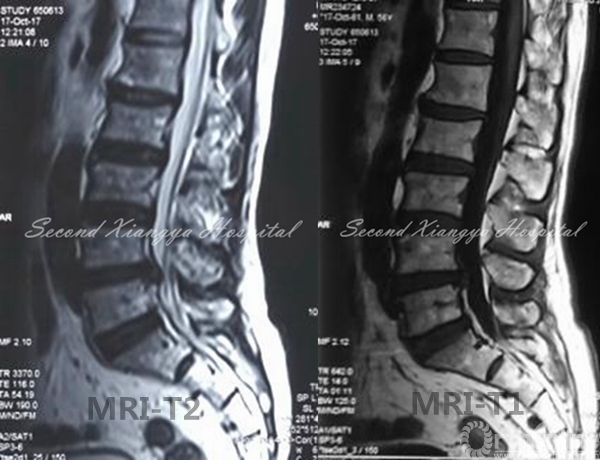

4.L4/5及以上节段,用常规腹部拉钩将将腹主动脉和静脉向内侧牵开,但不用过中线;

血管拉开示意图

5.另一拉钩置于椎体侧前、交感神经链前方,将其稍向后牵开;

拉钩示意图